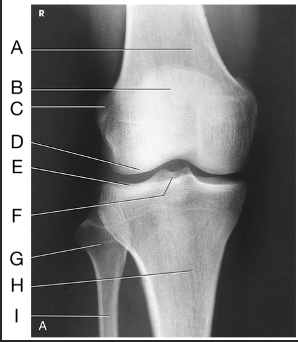

Name this projection

AP oblique medial rotation

What is demonstrated?

Lateral aspect (distal femur, patella, lateral tibial condyle, fibular head, and proximal tibiofibular joint)

What joint is demonstrated?

Proximal tibiofibular joint

Label the image: A

patella

Label the image: B

medial femoral condyle

Label the image: C

lateral femoral condyle

Label the image: D

medial tibial plateau

Label the image: E

Lateral tibial plateau

Label the image: F

medial tibial condyle

Label the image: G

lateral tibial condyle

Label the image: H

tibiofibular articulation

Label the image: I

fibula

Label the image: J

tibia